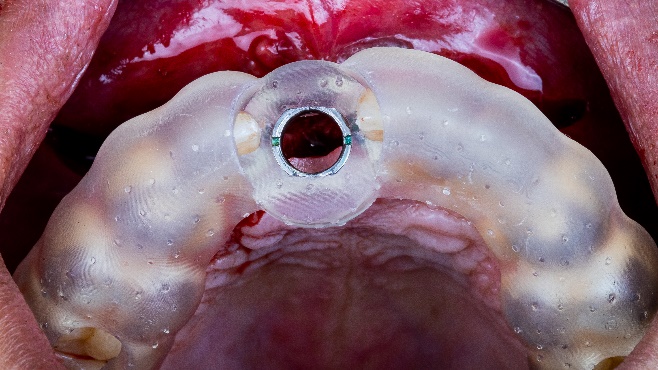

Хирургический шаблон был напечатан из прозрачного фотополимера с помощью 3D-принтера AccuFab-D1s от Shining 3D. Шаблон закрепили в полости рта, и он точно указал зону наращивания кости. Отверстие под имплантат было поэтапно просверлено через шаблон. Затем доктор вкрутил сам имплантат, который показал превосходную первичную стабилизацию. (Рис. 9, Рис. 10)

Рис. 9, Рис. 10: Установка имплантата с помощью хирургического шаблона.